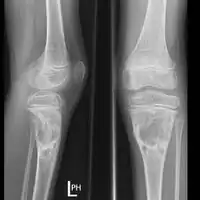

| Aneurysmal bone cyst (fibula, around knee). | |

X-ray: ABC large long bone of lower leg near knee